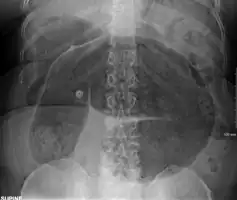

Coffee bean sign in a person with sigmoid volvulus -

An x-ray of a person with a small bowel volvulus.